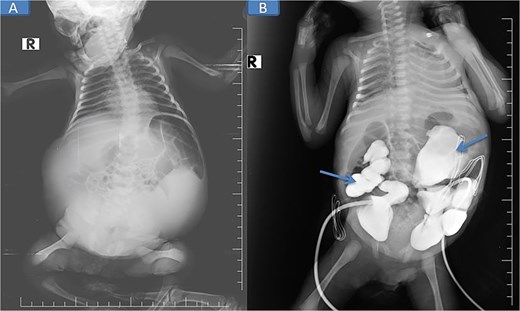

Pre-nephrostomy drainage abdominal distention (A) and post-nephrostomy (B).

Abdominal and scrotal ultrasonography demonstrated multilocular cystic hydronephrosis with thinning of renal parenchyma, extending into the pelvis, and absence of testes within the scrotum. Both testes were located intra-abdominally between bowel loops (left 7 × 4.5 mm, right 6 × 5.5 mm) (Figs 2 and 3). Abdominal X-ray after percutaneous nephrostomy with contrast revealed pooling in both kidneys without ureteric passage, suggesting bilateral ureteropelvic junction obstruction (UPJO) (Fig. 4).

Pre-op abdominal X-ray (A) and post-operative percutaneous nephrostomy procedure with contrast injection through the nephrostomy (B).